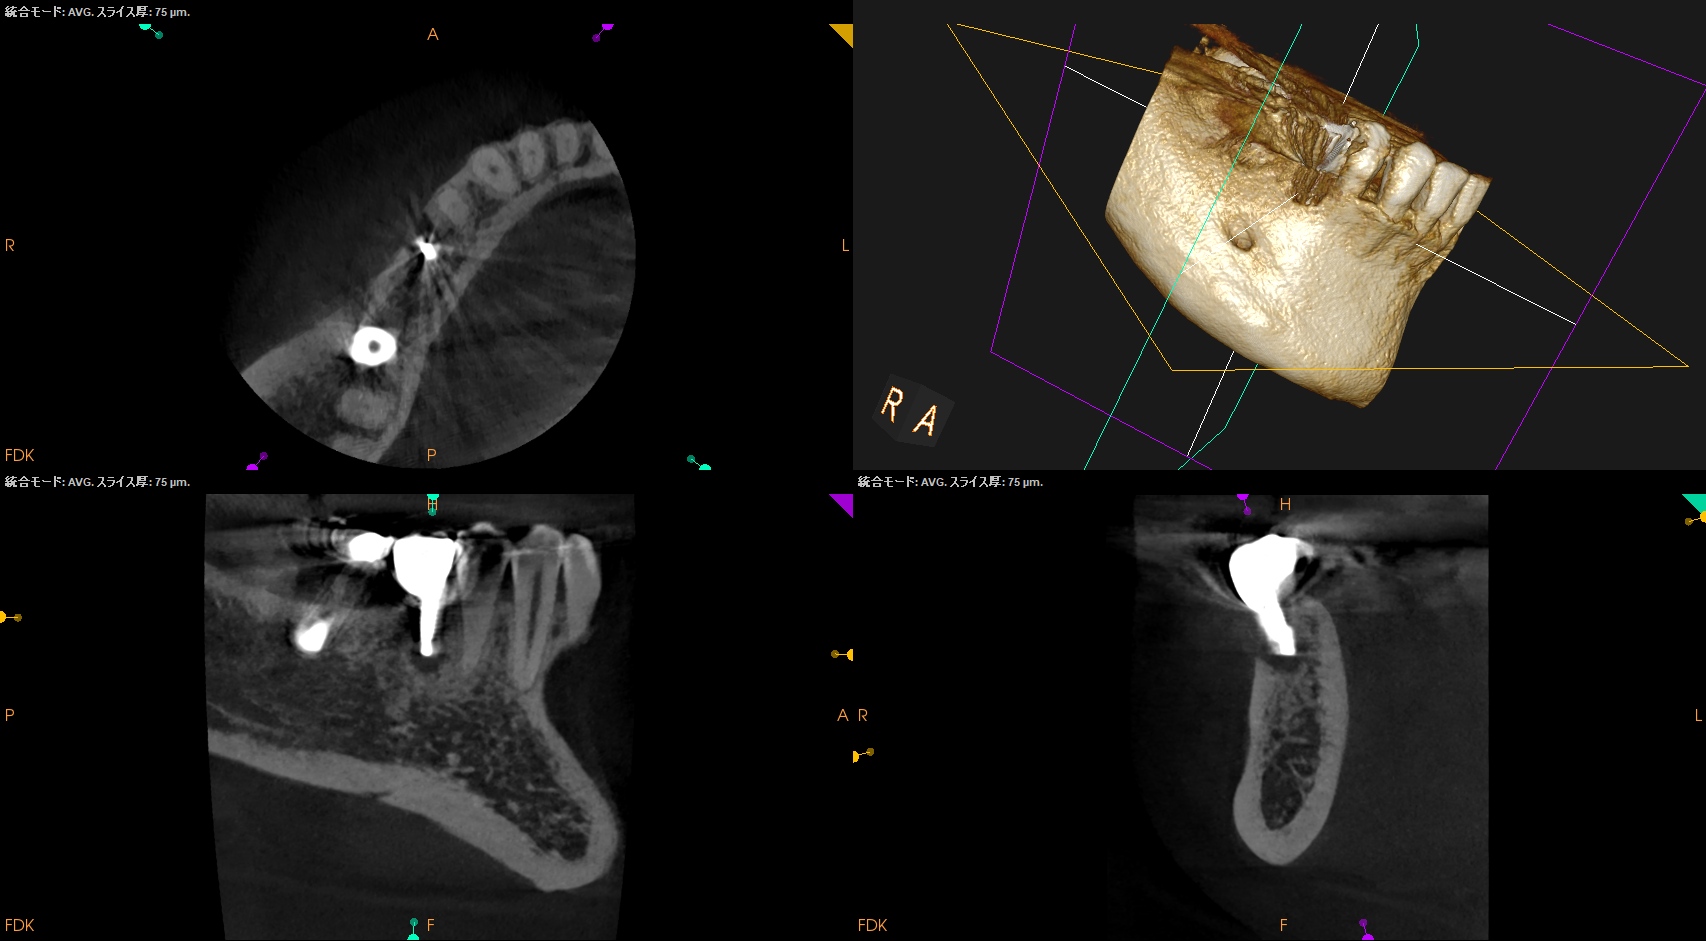

術後にPA, CBCTを撮影した。

問題はないだろう。